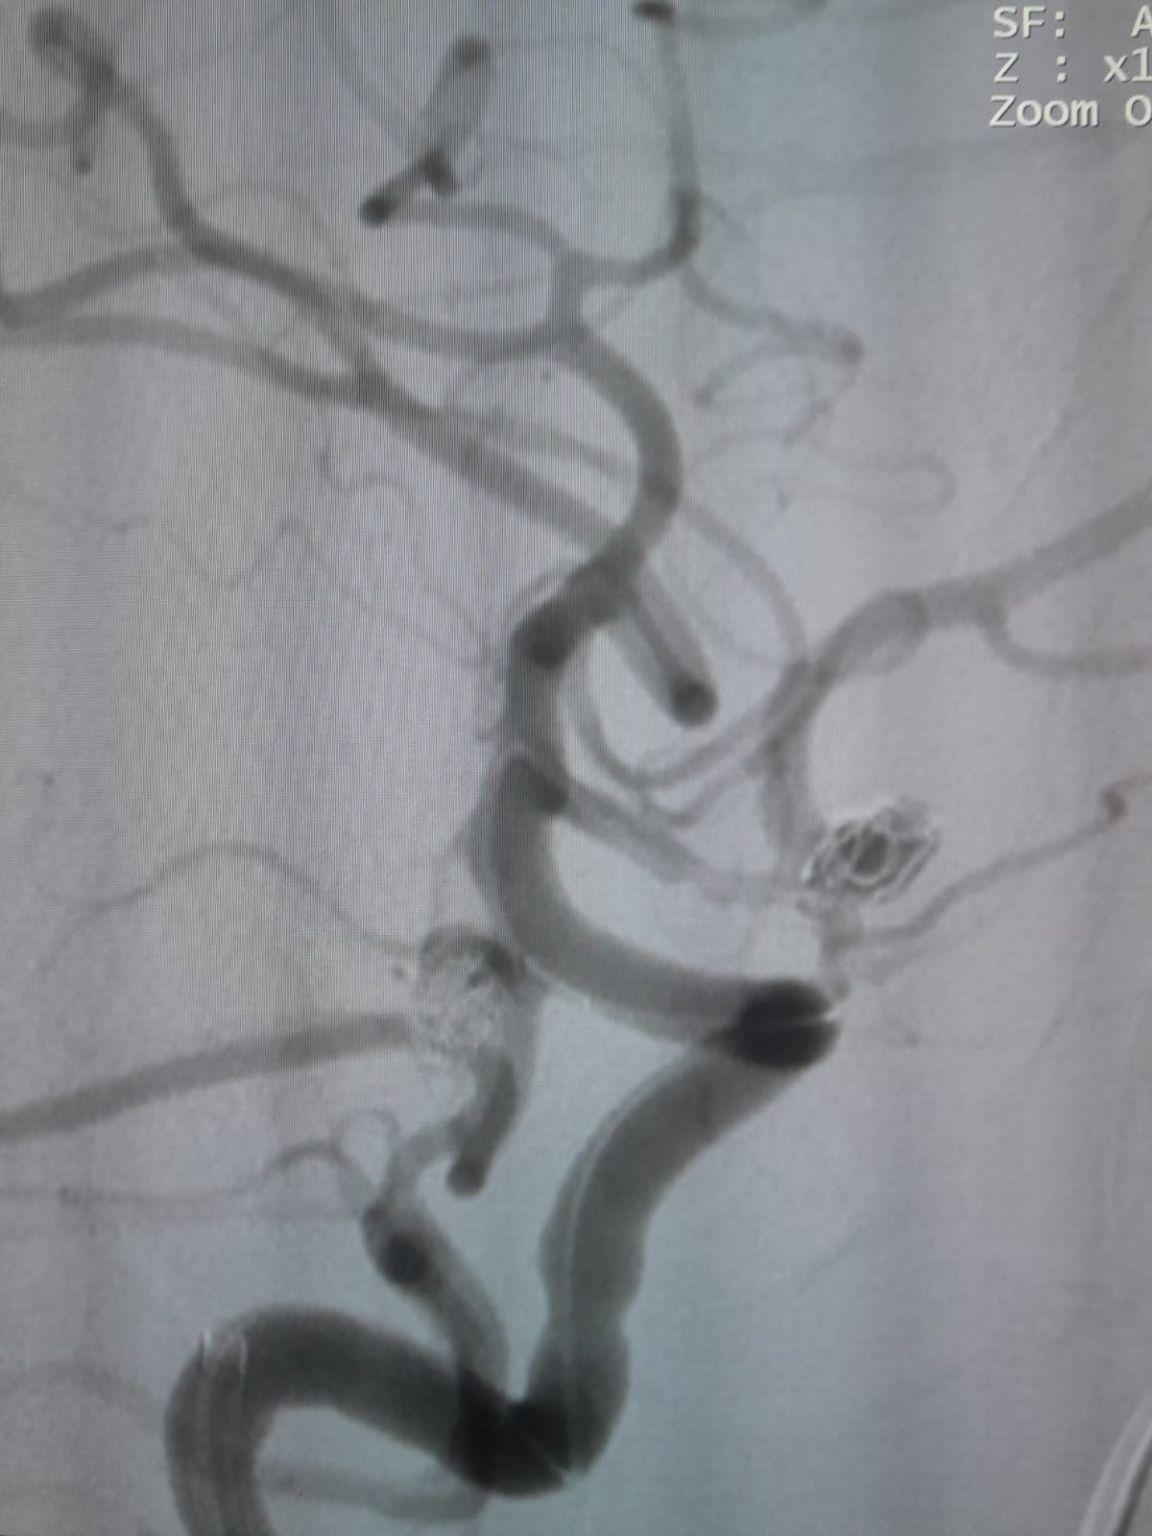

The patient was diagnosed with a newly discovered anterior communicating artery (AComA) saccular aneurysm and a posterior communicating artery (PComA) aneurysm that had been previously treated with coil embolization. Follow-up imaging revealed residual filling in the PComA aneurysm, requiring additional intervention.

The vascular access was established and the team then successfully navigated the Frepass® Disposable Microcatheter (TJMC14) to the target site. Embolization was performed using three Perdenser® Embolic Coil System (TJCST4.508-3D, TJCST0306-3D, TJCST0206-3D) deployed with the Deromper® Coil Detachment Controller (TJCDC).

Posterior Communicating Artery Aneurysm (Re-treatment)

During follow-up, residual filling was noted in the previously treated posterior communicating artery aneurysm. The team re-accessed the site using Frepass® Disposable Microcatheter (TJMC18 Plus) and successfully deployed a Nuva® Flow Diverter (TJED-D-4.5-16), which demonstrated ideal wall apposition and excellent flow diversion, leading to highly satisfactory treatment outcomes.